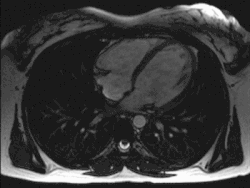

![]() Un trasplante de corazón pone a todo el mundo ante dilemas éticos. | |||||